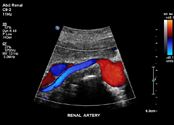

vaskular.pdf